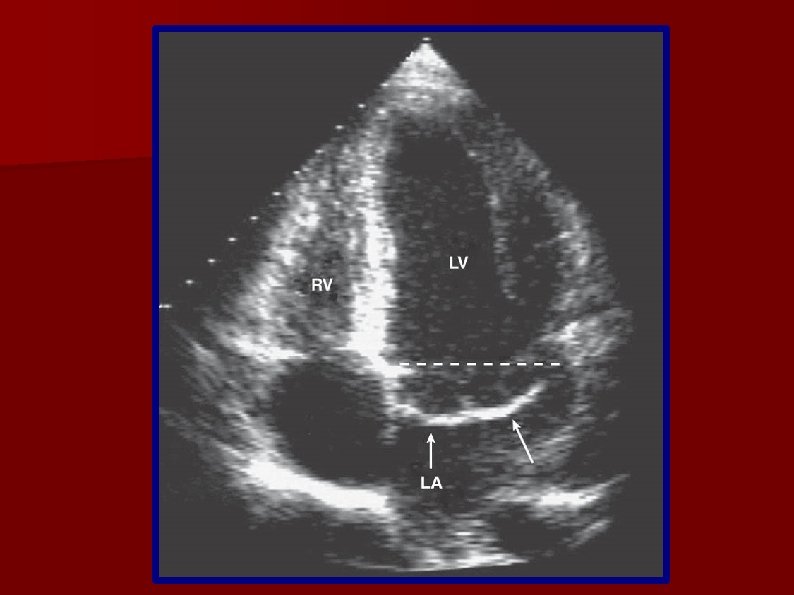

Papel del ecocardiograma en la reparación mitral Cirugía Cardiovascular Prolapso Y Insuficiencia Mitral la insuficiencia mitral puede ser primaria (son causas frecuentes el prolapso de la válvula mitral y la fiebre reumática) o. prolapso de la válvula mitral e insuficiencia valvular. la insuficiencia mitral es la complicación más frecuente del prolapso de la válvula mitral. el prolapso de la válvula mitral es un trastorno por el cual las solapas. Prolapso Y Insuficiencia Mitral.